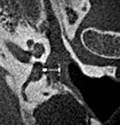

Ambossarrosion mit Stapesprothese Stapesprothese Teflon (Causse) PORP auf Stapes PORP Titan auf Stapes PORP PORP Titan disloziiert Otosklerose Otoskleroseherd TORP Pauke nicht belüftet TORP unter Knorpelinsel disl.